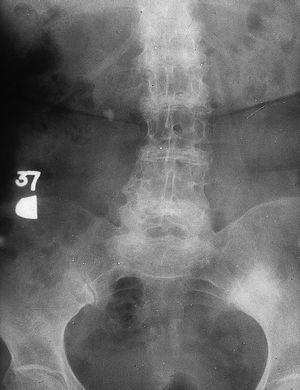

En la serie radiológica del esqueleto axial se aprecia calcificación y osificación de los discos intervertebrales con pinzamientos del espacio articular y fenómenos de vacío en los discos, osteopenia de los cuerpos vertebrales, así como afección de sínfisis púbica y menos frecuente de las sacroilíacas (fig. 1).

Fig. 1

En el esqueleto axial llama la atención la calcificación del disco, sobre todo a nivel dorsolumbar, pinzamiento del espacio intervertebral con colapso del disco y consiguiente fusión, y formación de cuerpos intervertebrales marginales.